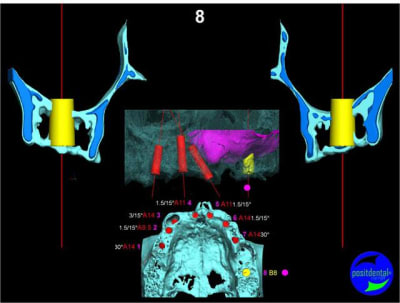

Extraction, pose d’implants Ankylos, pose des piliers Standard définitifs, mise en charge immédiate bi-maxillaire en une chirurgie.

Maxillaire supérieur – extraction 13, 26, 7 implants en MCI, 1 implant en MCR pose summeurs, densification par ostéotme, comblement osseux, bridge provisoire sans fausse gencive avec renfort métallique.

Maxillaire inferieur – extraction 35, 34, 44, 45, 6 implants MCI, comblement osseux, bridge provisoire sans fausse gencive avec renfort métallique.

en attendant la pano voici les coupes de la S.I.A.O.